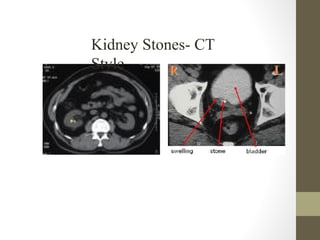

Radiology- CT Scan

• Detect leaking AAA (in stable patient)

• Evaluate for renal calculi, appendicitis, perforation (free air),

diverticulitis, abscess, mesenteric ischemia, masses, obstruction

• Sensitivity and specificity vary

• Not a place for unstable patients

• Contrast

• PO and IV contrast in most patients

• sometimes rectal contrast is helpful to look for large bowel problems

(appendicitis)

• In patients with renal insufficiency

• give IV contrast judiciously in patients

• consider ultrasound as an alternative if possible

• a creatinine > 1.5 usually requires bicarbonate and fluid hydration to

minimize contrast nephropathy

Kidney Stones- CT

Style

Rapid Case #18

• 28 yo post-partum healthy female

• Acute R flank pain radiating to groin

• Exam: Abd soft, non-tender without CVA tenderness

• UA with 2+ RBC, no WBCs

• CT with R Ureteral Calculi

• Dx: Renal Colic

Radiology- CT Scan •Detect leaking AAA (in stable patient) • Evaluate for renal calculi, appendicitis, perforation (free air), diverticulitis, abscess, mesenteric ischemia, masses, obstruction • Sensitivity and specificity vary • Not a place for unstable patients • Contrast • PO and IV contrast in most patients • sometimes rectal contrast is helpful to look for large bowel problems (appendicitis) • In patients with renal insufficiency • give IV contrast judiciously in patients • consider ultrasound as an alternative if possible • a creatinine > 1.5 usually requires bicarbonate and fluid hydration to minimize contrast nephropathy